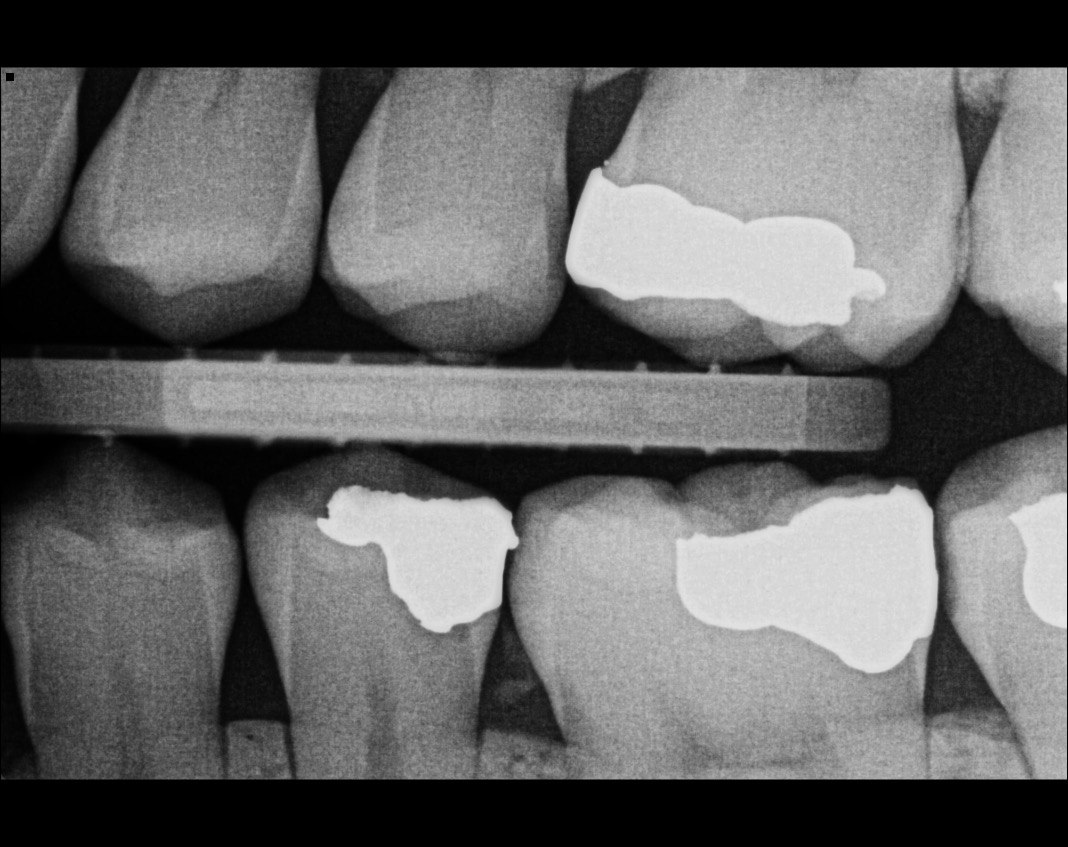

41. What options can be selected for the following X ray?

42. What is the caries on mesial surface of the tooth # 3.6?

43. Which surfaces require restoration?

44. What is the condition on distal surface of the tooth # 4.4?

45. What is the condition on mesial surface of the tooth # 1.5?

46. which teeth shows evidece of occlusal recurrent caries?

47. Which option does not describe the X ray bellow correctly?

48. Which tooth shows recurrent caries?

49. Which surface shows a RA1 caries?

50. Which option is evident on the print of the X ray?